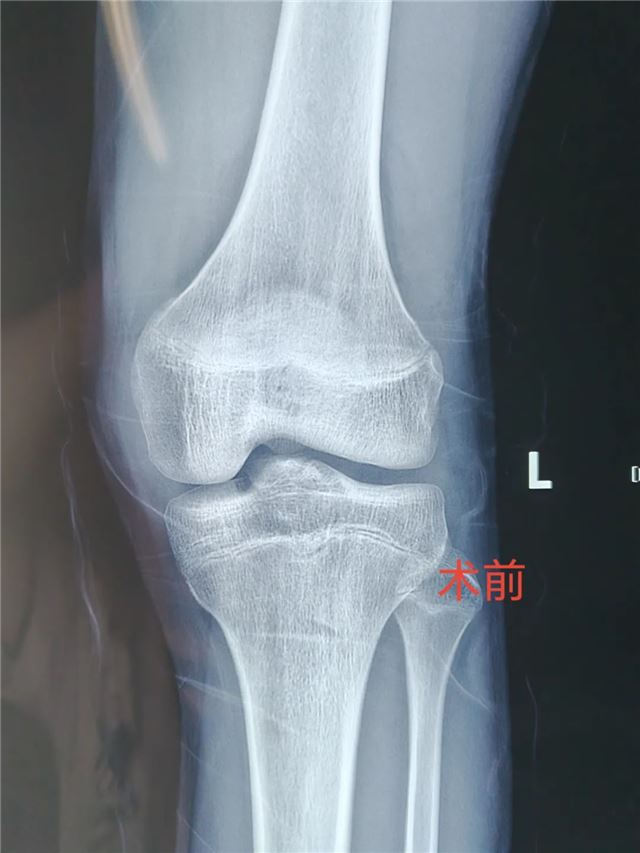

近日 长治二院小儿骨科团队 成功完成首例 关节镜下胫骨髁间棘骨折复位固定手术 标志着 长治二院小儿骨科 在青少年运动损伤及关节 微创治疗领域又上新台阶! 术前 术中 该手术通过仅0.5cm的微小切口,结合高清关节镜技术,实现骨折精准复位与牢固固定,术后患者无疼痛、恢复快,早期可下地活动,为青少年患者提供了更优治疗方案。 技术亮点 创伤极小:避免传统开放手术的大切口,减少软组织损伤。 精准高效:关节镜高清视野助力精准复位,固定牢靠。 康复迅速:术后早期功能锻炼,缩短住院时间,降低并发症风险。 美观无忧:微创切口隐蔽,术后疤痕几乎不可见。 适应人群 运动损伤致胫骨髁间棘骨折患者。 膝关节外伤后疼痛、活动受限者。 追求微创、快速康复的青少年患者。 咨询电话: 主任医师任泽恩:13008078999 周一、周五、周六上午专家门诊 主治医师牛佳伟 18834181790 周日上午节假日门诊 科普园地 01 胫骨髁间棘骨折是什么? 胫骨髁间棘是膝关节内交叉韧带附着的重要结构,骨折多由运动损伤(如急停、扭转)或高能量外伤(如车祸)导致,表现为膝关节剧痛、肿胀、无法伸直,易误诊为韧带损伤。 02 传统手术 vs 关节镜微创手术 传统开放手术:需切开关节囊,创伤大、恢复慢,可能遗留关节僵硬。 关节镜手术:通过2-3个5mm小孔完成,镜下精准复位骨折块,配合可吸收螺钉或缝线固定,最大程度保护关节功能,术后可早期开始康复锻炼。 03 术后康复小贴士 早期冰敷+踝泵训练,减轻肿胀 术后2周内拄拐部分负重,逐步过渡到全负重 4-6周后结合理疗加强膝关节活动度与肌力 微创技术,让运动之痛不再成为人生绊脚石!长治二院小儿骨科将持续深耕关节微创领域,以尖端技术守护儿童“膝”望! 名医推荐 任泽恩 主任医师、教授 骨科党支部书记 小儿骨科病区主任 硕士研究生导师 牛佳伟 主治医师 骨科学硕士 【专业特长】 儿童创伤保守和手术的微创治疗。四肢畸形矫正(先天性或创造成的肢体内外翻、肢体不等长等)。手足部多指/趾畸形、并指/趾畸形等。曾于北京参加“骨外固定与肢体重建基础实战技术培训班”。 科室简介 小儿骨科于2019年创立,现病床配置18张,科室现有主任医师1名,副主任医师1名,主治医师1名,住院医师1名,其中硕士研究生2名,硕士研究生导师1名,目前是长治地区唯一专业诊治儿童骨骼疾病的专业科室,年门诊量5000余人次,年手术近500例。 科室成立5年来,我们小儿骨科团队同心协力,追求卓越,推动学科快速发展。我们小儿骨科开展的多项手术技术处于省内领先地位,辐射影响达周边地市,在上党地区享有盛誉,得到了国内、省内业内同行及患者家属的高度认可。目前以京长合作为契机积极与北京积水潭医院小儿骨科紧密合作,成立了“吕学敏教授团队名医工作室”,定期派专家来我院坐诊、讲学、查房,开展新技术新项目、疑难病例会诊及手术指导。大大提高了诊疗疑难疾病的能力。 诊疗范围:14周岁以下的儿童骨病患者(含14周岁)。目前已经开展的技术项目:小儿四肢关节创伤微创手术治疗、部分小儿先天性及发育性畸形矫正、四肢与关节特异性及非特异性炎症、儿童各类软组织疾患及骨肿瘤。(肱骨髁上骨折闭合复位经皮克氏针内固定、儿童四肢骨干骨折弹性髓内针内固定、青少年股骨干骨折交锁髓内钉内固定、肘关节关节内骨折手术治疗、手足多指(趾)畸形切除及矫形术)。 编 辑丨翟艳鹏 初审初校丨牛佳伟 复审复校丨任泽恩 终审终校丨雷 赫